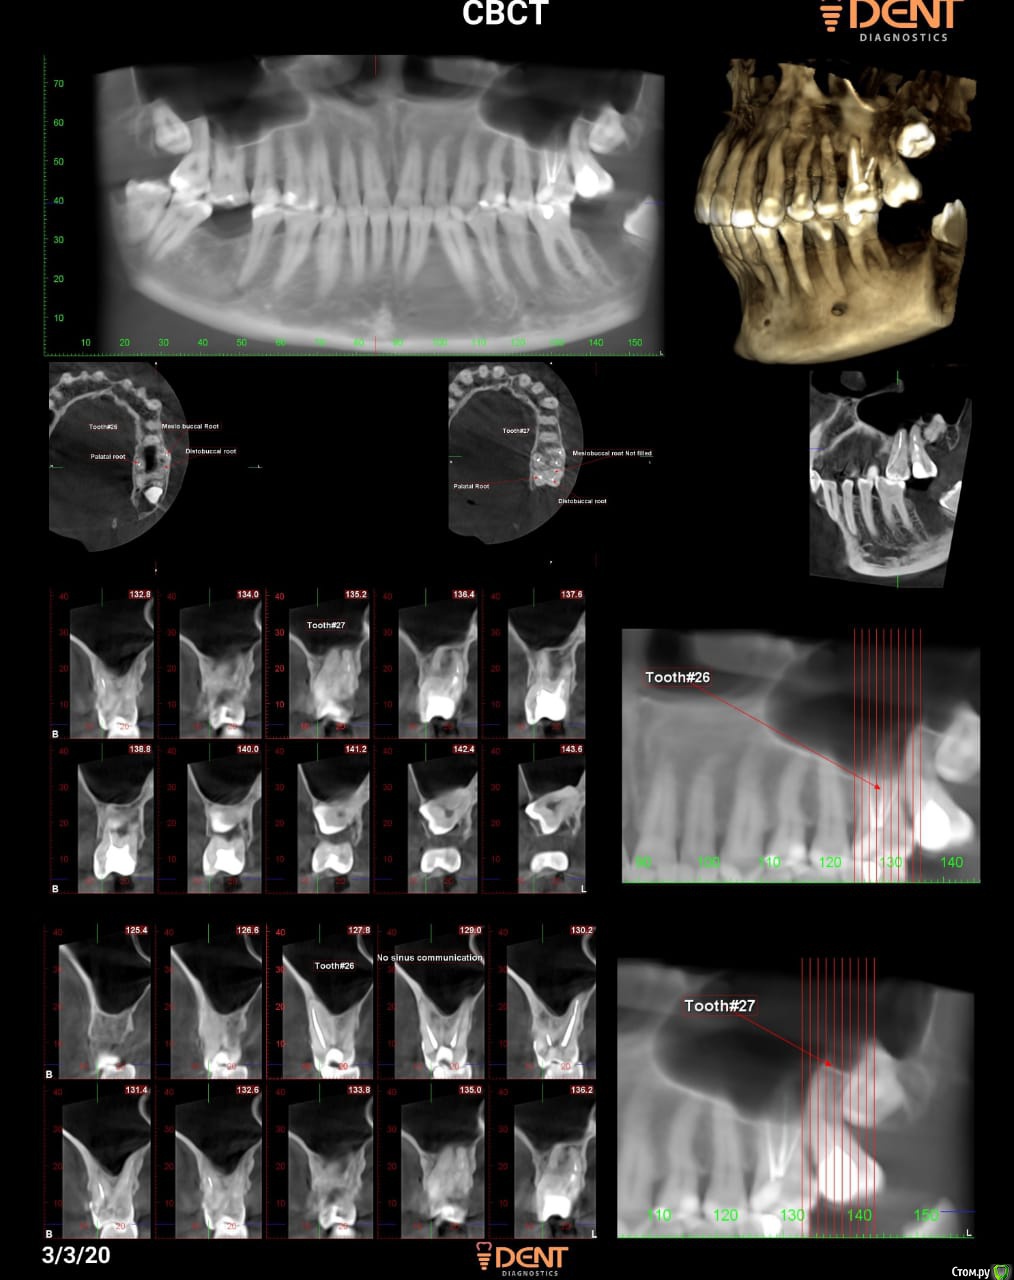

Natalira Опубликовано 15 марта, 2020 Поделиться Опубликовано 15 марта, 2020 (изменено) Здравствуйте,уважаемые стоматологи .помогите разобраться с 26 зубом . В январе 15 года поставили пломбу на жевательную поверхность и закрыли совсем небольшой клиновидный дефект . Зуб заболел через неделю. Врач наносил лак и прописал месяц пить кальций . В 2018 году февраль . Тот же характер болей , но сильней . Я уже в другом городе . Другой врач по сделанному панорамному снимку , ставит диагноз пародонтит( но небольшой как он сказал карман ,совсем маленький ) , чистит карман выписывает антибиотики . Через месяц все проходит . На следующих плановых осмотрах все норм с этим зубом . Январь 2020 заболел 37 зуб, лечение , чистка каналов , абсцесс , удаление ,антибиотики. Через 2 недели после удаления заболел 26.опять чистят карман , через два дня настаиваю на вскрытии каналов ( уже исходя из недавнего опыта с 37 , кот также изначально заболел в 15 году после пломбировки , тогда врач сказал нечему болеть и уже в итоге Переодонтит хронический ). Врач вскрывает каналы , говорит нерв мертв . Придти через 5 дней . Опять чистит каналы ,ставит временную пломбу говорит придти через 10 дней . Прихожу ,говорю что есть ещё боли,но не всегда и незначительные . Прошу поменять лекарство , говорит что в моем случае нет необходимости . Я говорю что переживаю ,что хронический Переодонтит был 4 года . Врач уверено говорит что будет пломбировать каналы и пломьирует , делает снимки ( 4 раза переснимал),говорит что все хорошо. И что приходить через месяц перелечивать 27 зуб . Но он не болел ни разу , несмотря на плохо запломбированный каналы ( врач сказал по снимку) и он так уже минимум 20 лет . Изначально 26 и 37 начинала лечить в России. ССейчас лечу по месту жительства . Программный снимок так же есть до удаления 37 зуба . В 26 временами возникают неприятные ощущения . Боль в районе корня стихает . Врач сказал ,что со временем пройдет . Извините за ошибки ,пишу с телефона . PS: КТ было сделано с временной пломбой , до пломбировки каналов гуттаперчей Изменено 15 марта, 2020 пользователем Natalira Ссылка на комментарий

Natalira Опубликовано 16 марта, 2020 Автор Поделиться Опубликовано 16 марта, 2020 Спасибо за ответ , после пломбировки финальной КТ не делала . Мой вопрос , исходя из панорамного снимка и КТ какой был диагноз. Правильно ли было предложено и проведено лечение исходя из снимков . Не слишком ли быстро были запломбированы каналы. Мои переживания , могла ли остаться инфекция после удаления нервов из зуба и временной пломбы , антибиотики я также пропила 10 дней Аугментин и метротенидазол . Очень сложно найти контакт с лечащим врачом , даже элементарно не хотят говорить ,что было заложено в каналы на 12 дней для лечения. Ссылка на комментарий

Natalira Опубликовано 16 марта, 2020 Автор Поделиться Опубликовано 16 марта, 2020 (изменено) И как часто можно делать КТ? У у нас даже не одевают защитный фартук , ни для панорамного снимка ни для КТ.внутриротовые снимки врач делал 4 штуки после финальной пломбировки .сказал что все нормально запломбированы . Но они у него .на мои жалобы на брль в области корня зуба , сказал что со временем пройдет . На панорамном снимке он увидел что между 26 и 27 что когда то был абссец в районе черного пятна . Я не знаю как это понимать . 2 года назад ,он болел , но другой врач ничего не нашел по панорамномному снимку ,2 годичной давности тоже снимок есть . За 2 месяца я уже просто морально и физически устала и от болевых ощущений и от моральных . Изменено 16 марта, 2020 пользователем Natalira Ссылка на комментарий

Natalira Опубликовано 16 марта, 2020 Автор Поделиться Опубликовано 16 марта, 2020 (изменено) Это уже третий врач .но 26 лечил один врач Не все так просто у нас с врачами. Поэтому Пишу с надеждой на помощь на форуме.Снимки он мне не дал на руки. Многие просто отказываются даже смотреть КТ. Панорамный делала 28 января , через месяц КТ. Как часто можно делать такие обследования ? Но хотябы из моих снимков что с 26 зубом был периодонтит или просто пульпит ? Очень надеюсь на консультацию . Изменено 16 марта, 2020 пользователем Natalira Ссылка на комментарий